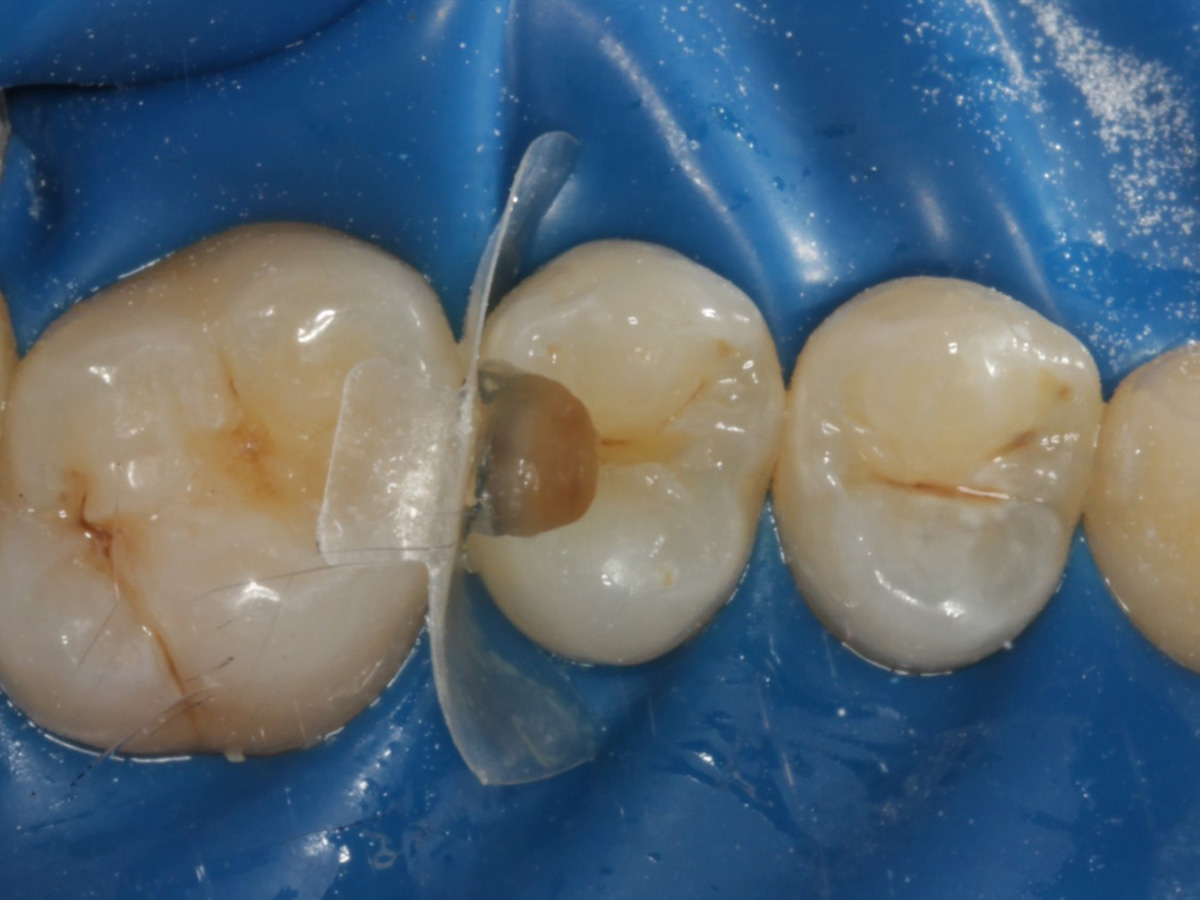

Abbildung 10

Nach Applikation der Matrize: Evolve Schwarz Prämolar- 7 mm; Schmelzätzung

Abbildung 11

Nach Spray und Trocknung der Kavität

Abbildung 12

Nach erneuter Applikation des Einkomponentenadhäsivs und tief approximal eines fließfähigen Bulkkomposits, der Lichthärtung, und der Applikation des Bioclear Diamond Wedges Medium